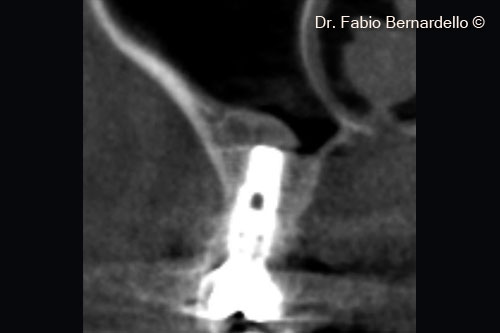

Hình ảnh toàn cảnh xoang hàm trên (Panorex) tại thời điểm ban đầu T0. Gel 40 nâng màng xoang ở vị trí cấy ghép mới và cả phía trên đỉnh của implant cũ ở vị trí số 16

Hình ảnh CBCT mặt cắt ngang tại thời điểm ban đầu (T0). Gel 40 nâng màng xoang tại vị trí cấy ghép mới và cả phía trên đỉnh của implant cũ ở vị trí số 16